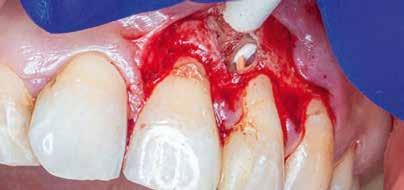

A 28 éves pácienst gyulladásos IRR kezelése céljából irányították a rendelőnkbe. A jobb felső nagymetszőfogáról készített periapikális röntgenen egyértelműen látható volt a lézió. A várható prognózis megállapítása, valamint kezeléstervezés céljából az érintett területről CBCT-felvétel készült (8. a–e ábra). A háromdimenziós képen látható volt a gyökér labiális falán lévő perforációs nyílás, valamint az ezt körülvevő bukkális kortikális destrukciója. A terület sebészi feltárását a bal felső nagymetszőfogtól a jobb felső szemfogig intrasulcularisan vezetett metszésből végeztük el. A lebeny elemelését követően egy exkavátor segítségével eltávolítottuk a reszorbciós üreget kitöltő granulációs szövetet (9–11. ábra), majd hagyományos

8. a–e ábra: A kiindulási röntgen (a) és a kiindulási állapotról készített CBCT-felvétel (b–e). A felvételen jól látható a csatornafal és a bukkális kortikális perforációja.

8a 8b 8c 8d 8e

perforáció